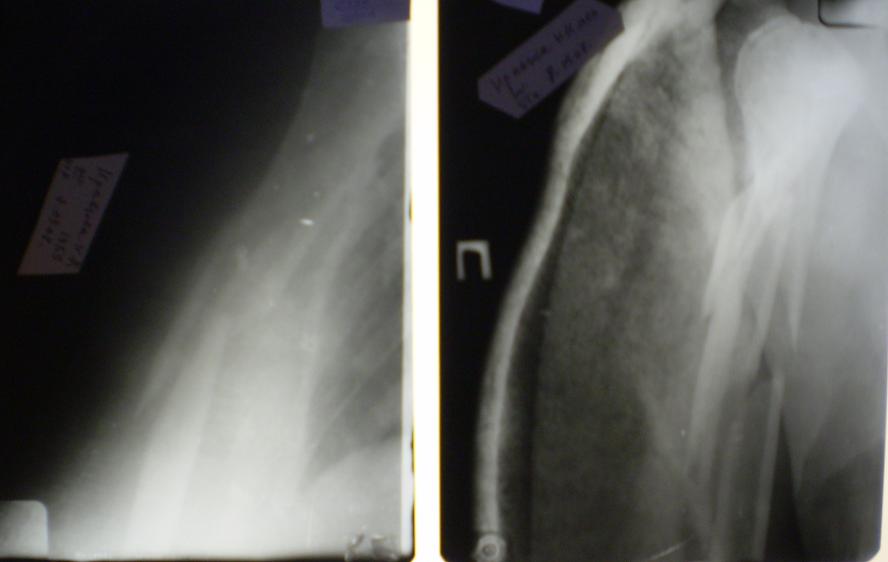

[Ortho] Многооскольчатый перелом плечевой кости в В/3

Вот снимки покачественнее, отсканировал.